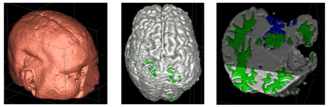

Case 1: Segmentation of 5channel TBI data with ABC. Lesions and ventricles segmented with additional 3D level-set segmentation.

Case 2: Segmentation of 5channel TBI data with ABC. Lesions and ventricles segmented with additional 3D level-set segmentation.

Case 3: Segmentation of 5channel TBI data with ABC. Lesions and ventricles segmented with additional 3D level-set segmentation.